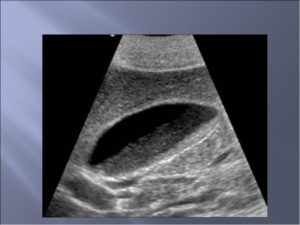

На УЗИ желчного пузыря различают несколько форм билиарного сладжа:

- эховзвесь – начальные признаки сладжированной желчи;

- билиарные сладж-сгустки – наличие мелких образований;

- особые формы – полипы из холестерина, замазкообразная желчь при атонии полого органа, конкременты до 0,1-0,2 см.

- УЗИ желчного пузыря позволяет определить анатомические параметры и оценить состояние органа, выявить холестаз, холестероз, фиброз, сгустки, конгломераты, хлопьевидный осадок в желчи, определить ее количество. До сих пор ученые-медики не определили, является ли сладж синдром самостоятельным заболеванием или только УЗИ-симптомом. Это связано с отсутствием прогноза патологии, эффективных лечебных схем и тактики ведения пациентов.

Назначение оптимального лечения требует провести обследование. Гастроэнтеролог должен обнаружить аномалию на ранней стадии. Первым назначаемым обследованием обычно бывает УЗИ, где определяется тип сладжа (осадка). Состав и классификация осадка условно разделяет взвеси на три типа:

- Микролитиаз (эхогенная взвесь) – эта взвесь состоит из небольших частиц (хлопьев), легко перемещающихся;

- Замазкообразная желчь – здесь наблюдаются сгустки различной плотности с отчетливыми очертаниями, которые также легко перемещаются;

- Микролитиаз с густой желчью (гиперэхогенная взвесь) – эта взвесь состоит из сгустков желчи, сладжей, обнаруживается обычно в задней части ЖП (сочетает в себе признаки первых двух групп).